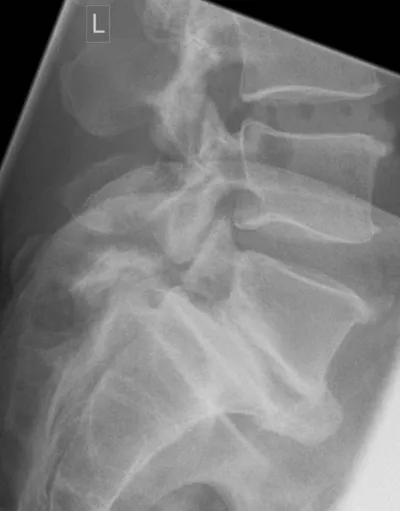

Pars Interarticularis Radiology Images

Browse 2 medical images tagged with pars interarticularis. This collection includes various imaging modalities for medical education and reference.

This collection contains 2 radiology images related to pars interarticularis, including various imaging modalities such as X-rays, MRIs, CT scans, and ultrasound images commonly used in medical diagnosis and education.